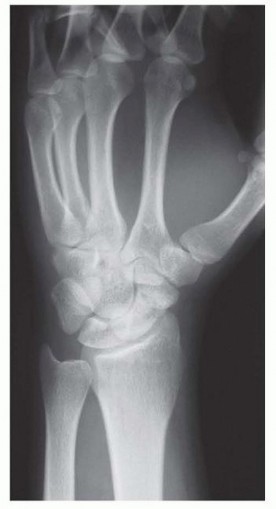

Pre-Operative Planning, Templating, and Patient Positioning

Thorough preoperative planning is what separates an adequate surgeon from a master surgeon. The evaluation begins with a rigorous imaging protocol. Standard posteroanterior (PA), lateral, and specialized scaphoid views (45- and 60-degree pronated oblique views) are mandatory to assess the fracture orientation, degree of displacement, and the presence of any early degenerative spurring at the radial styloid. However, plain radiographs are insufficient for precise surgical templating. A high-resolution Computed Tomography (CT) scan, reformatted in the true sagittal and coronal planes of the scaphoid, is the gold standard. The CT scan allows the surgeon to accurately measure the volumetric bone void, calculate the exact lateral intrascaphoid angle, and template the required dimensions of the corticocancellous wedge graft needed to restore anatomical length.

Furthermore, assessing the vascular status of the proximal pole is a critical preoperative step. While intraoperative assessment of bleeding bone is the ultimate test, a preoperative Magnetic Resonance Imaging (MRI) scan without and with intravenous gadolinium contrast provides invaluable predictive data. A proximal pole that enhances with contrast indicates viable intraosseous microcirculation, validating the plan for a non-vascularized volar wedge graft. Conversely, a dark, non-enhancing proximal pole on T1-weighted fat-suppressed contrast images signals avascular necrosis, prompting a shift in the surgical plan toward a vascularized bone graft. The MRI is also useful for ruling out concomitant soft tissue injuries, such as tears of the scapholunate interosseous ligament or triangular fibrocartilage complex (TFCC).